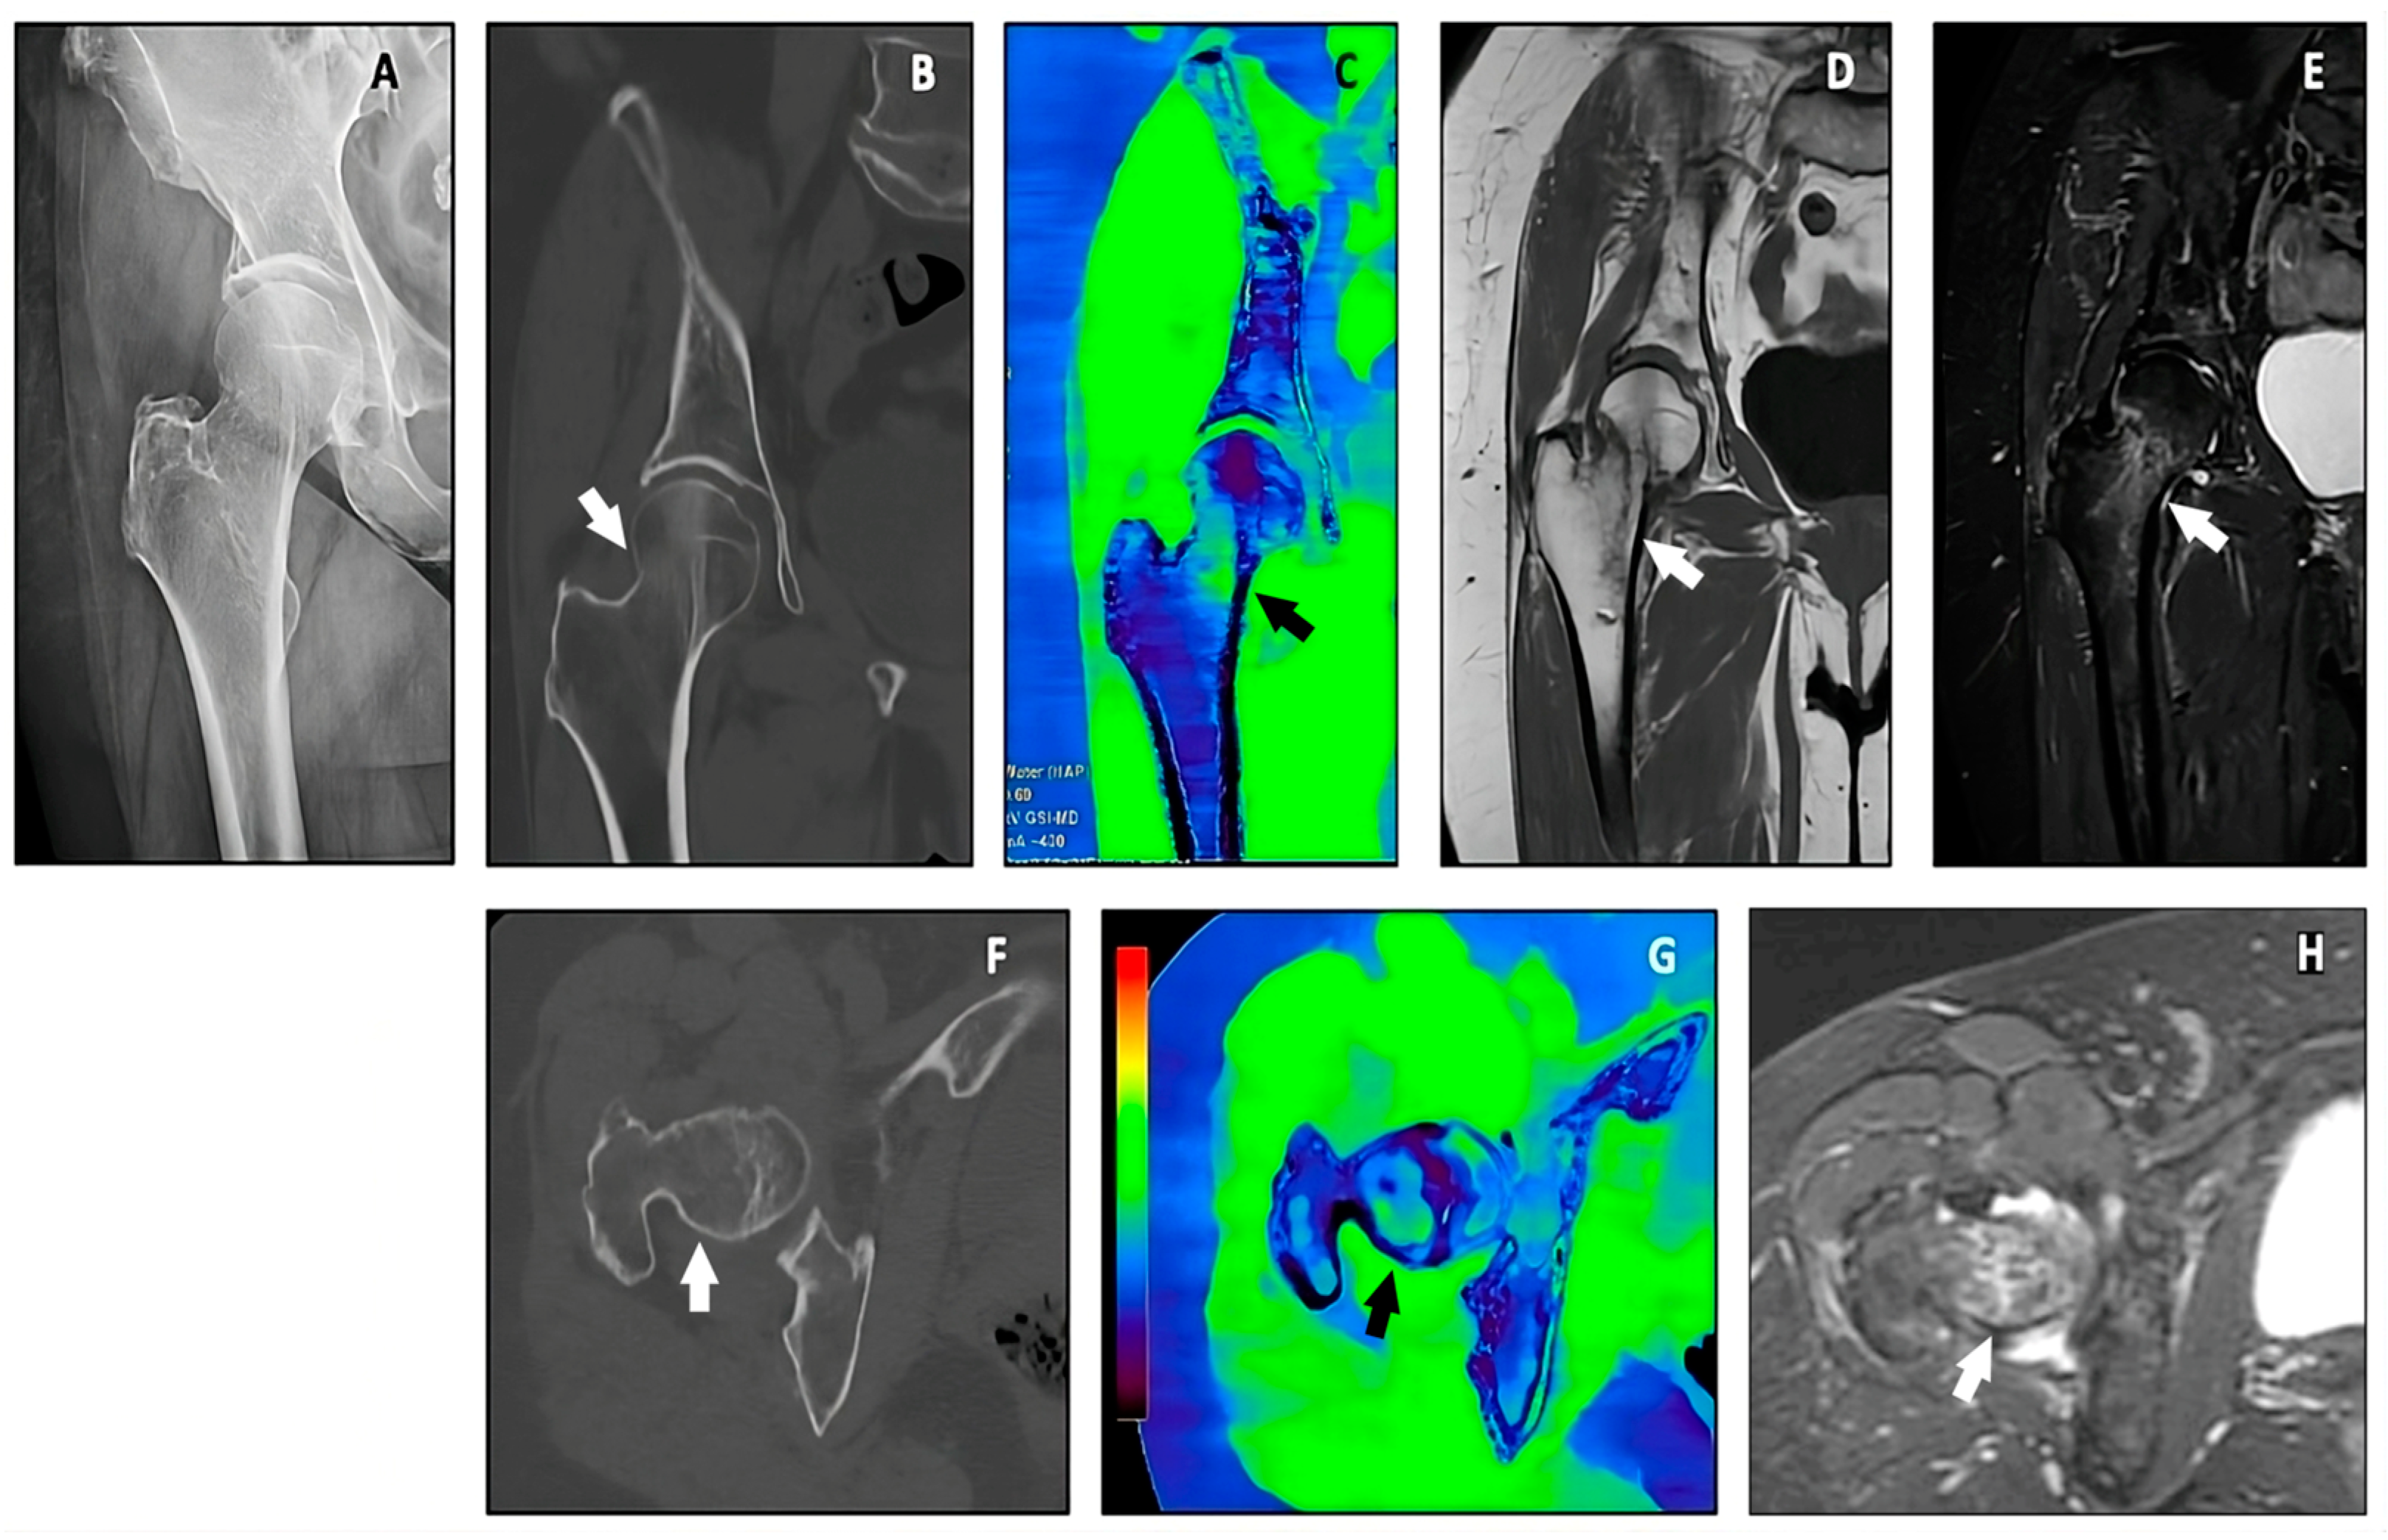

Toward the Application of Dual-Energy Computed Tomography with Virtual Non-Hydroxyapatite Color-Coded Maps to Identify Traumatic Fractures in Daily Emergency Settings

3. Results